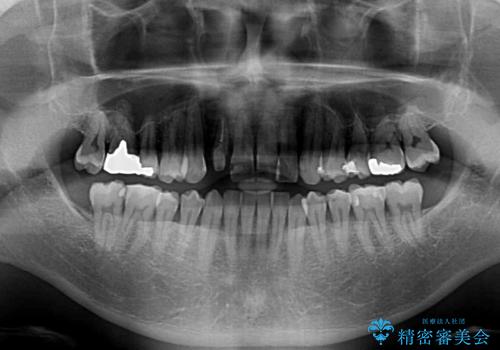

治療途中の前歯を治したい インビザライン矯正とオールセラミッククラウン

- 治療途中の前歯と上下前歯のデコボコ気にして来院された患者様です。

前歯のデコボコはインビザラインにより歯列を整え、その後に、前歯などをオーダーメイドタイプのオールセラミッククラウンにて補綴治療することとしました。